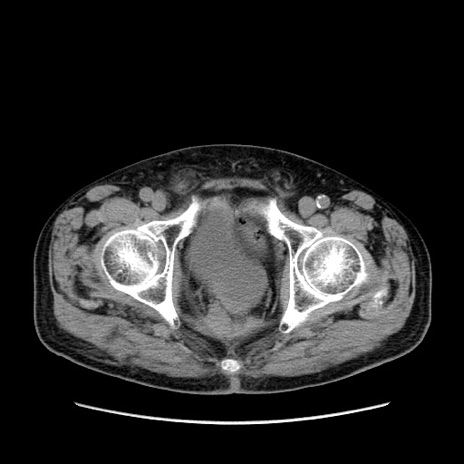

症例24(横断像)

【症例】80歳代男性

【主訴】左側腹部痛、嘔吐

【現病歴】本日早朝より左腹部に痛みあり。昼頃嘔吐認めたため、救急要請。

【既往歴】直腸癌(Mile手術)、胆摘

【身体所見】意識清明、BT 35.9℃、BP 221/93mmHg、SpO2 97%(RA) 、腹部:左ストーマ周囲に限局性の腹部膨隆あり。 膨隆部自発痛・圧痛あり・軟。

【データ】WBC 7700、CRP 0.09